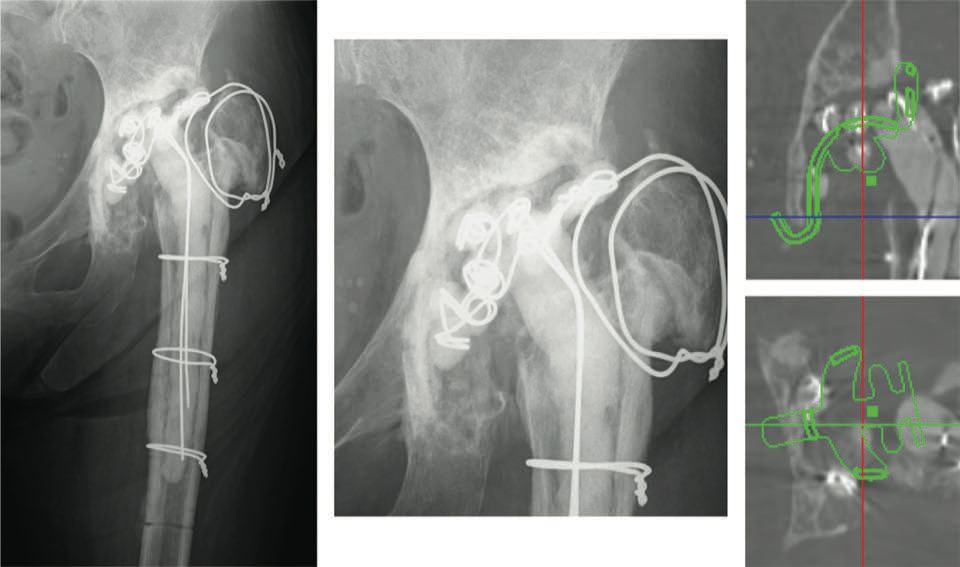

Preoperative planning is usually performed using software and scanned images in order to produce a 3D model (Kyocera) (Fig. 5).

The anterior-posterior diameter of the acetabulum determines the size of the KT cross. A pitfall to avoid is choosing a plate that is too large based solely on AP x-ray images. As shown in Case 1, the correct size and shape of the structural allograft can be estimated in advance, and the surgeon can determine the spatial relationship between the anatomical markers and the KT cross (Fig. 6).

This works as a guidance system. In Case 2, the medial wall and acetabular notch have been destroyed.

The medial wall, acetabular notch and weight-bearing zone need to be reconstructed. An angioscan can help avoid vascular complications by showing the acetabular markers and the vascularisation in the event of protrusion.